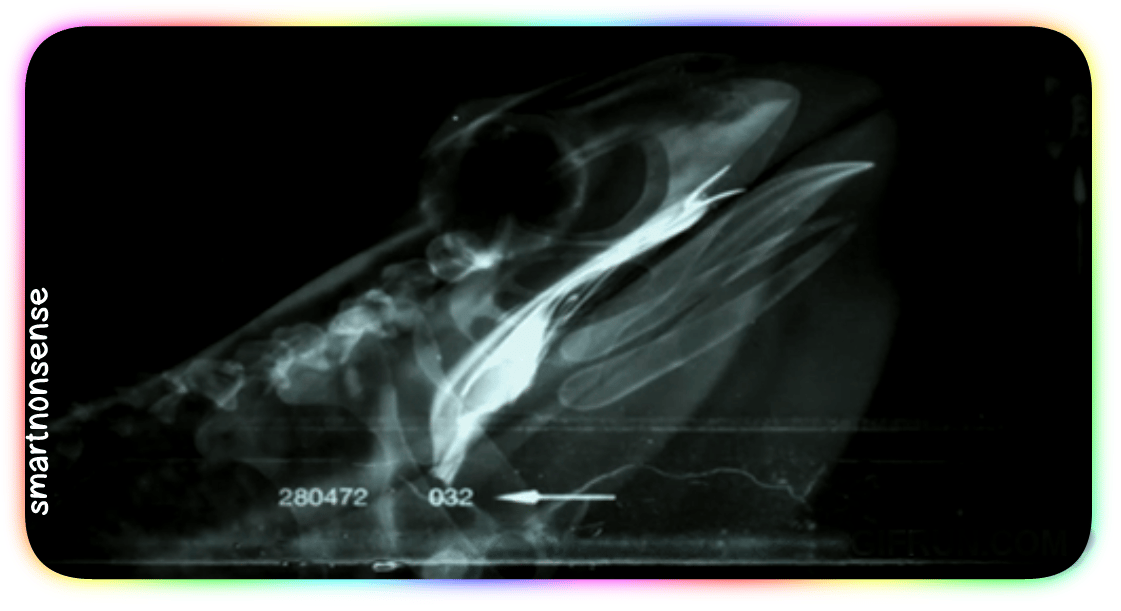

Check out this X-ray:

BANG.

When you go to swallow that fly, your eyeballs (which – you know – usually just sit in their sockets)

Get PULLED down by muscles

Into your skull!

They press HARD on the roof of your mouth:

Driving that meal straight down your throat!